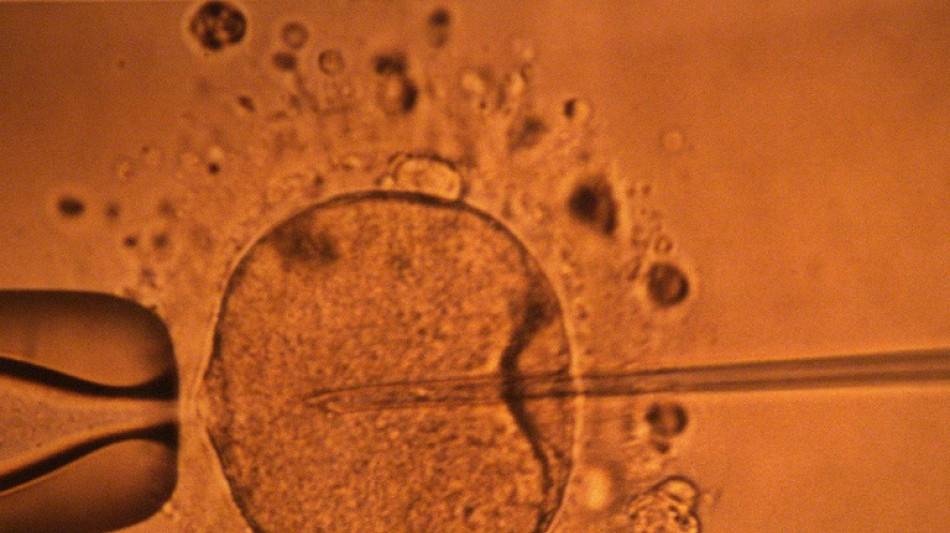

La concentración de espermatozoides, uno de los factores de la fertilidad masculina, disminuyó significativamente en todo el planeta en las últimas décadas, según un estudio publicado el martes.

"La concentración de espermatozoides disminuyó significativamente entre 1973 y 2018", resumen los autores de este trabajo publicado en la revista Human Reproduction Update y realizado mediante la compilación de unos 40 estudios previos.

La cantidad de espermatozoides es uno de los factores que afectan a la fertilidad masculina, pero no es el único.

Su movilidad también desempeña un papel crucial, pero esta característica no se mide en este estudio. Por ello, no se puede concluir que haya una disminución general de la fertilidad masculina, aunque la investigación aporta elementos en este sentido y se suma a otros trabajos que estudiaron las causas de esta tendencia.